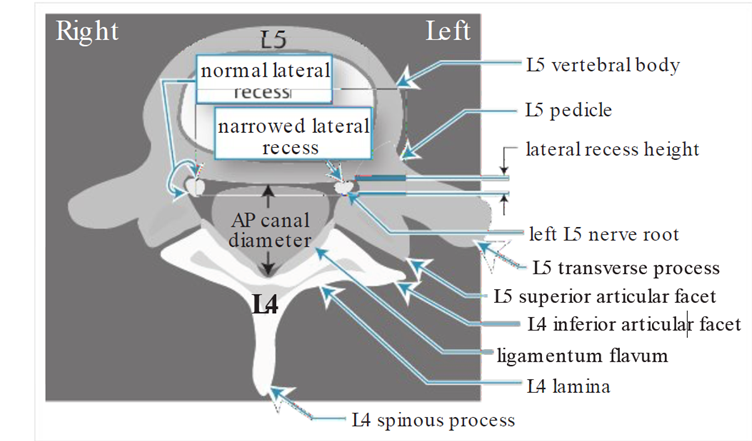

Ngách bên là cái “máng” kế bên cuống cung, nơi rễ thần kinh đi vào, nằm ngay cạnh vị trí rễ thoát ra khỏi lổ liên hợp, giới hạn trước là thân sống, giới hạn bên là cuống cung, và phía sau là mặt khớp trên của đốt sống dưới (hình 2). Mặt khớp này phì đại sẽ gây chèn ép rễ thần kinh. Hẹp ngách bên xảy ra ở tất cả các trường hợp hẹp ống sống trung tâm, nhưng hẹp ngách bên đơn thuần cũng có thể gây ra triệu chứng. L4-5 là mặt khớp hay bị nhất.

Hình 2. Scan cắt ngang mặt khớp L4-5 cho thấy ngách bên (bình thường bên phải và hẹp bên trái).